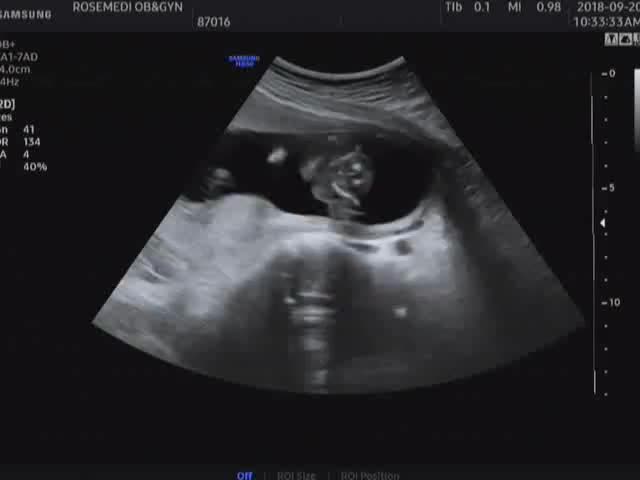

[임신기록] 29주.입체초음파

안녕하세요~ 오늘의 포스팅은 입체 초음파예요~ 어찌생겼을지 궁금 궁금 어찌 이리다 비슷할까요ㅎㅎ 모든 ...